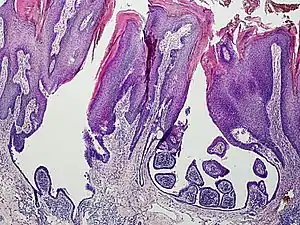

.png.webp) a) Syringocystadenoma papilliferum over a pre-existing nevus-sebaceous b) histopathology of syringocystadenoma papilliferum showing cystic invagination of surface epithelium

a) Syringocystadenoma papilliferum over a pre-existing nevus-sebaceous b) histopathology of syringocystadenoma papilliferum showing cystic invagination of surface epithelium An example of a syringocystadenoma papilliferum

An example of a syringocystadenoma papilliferum